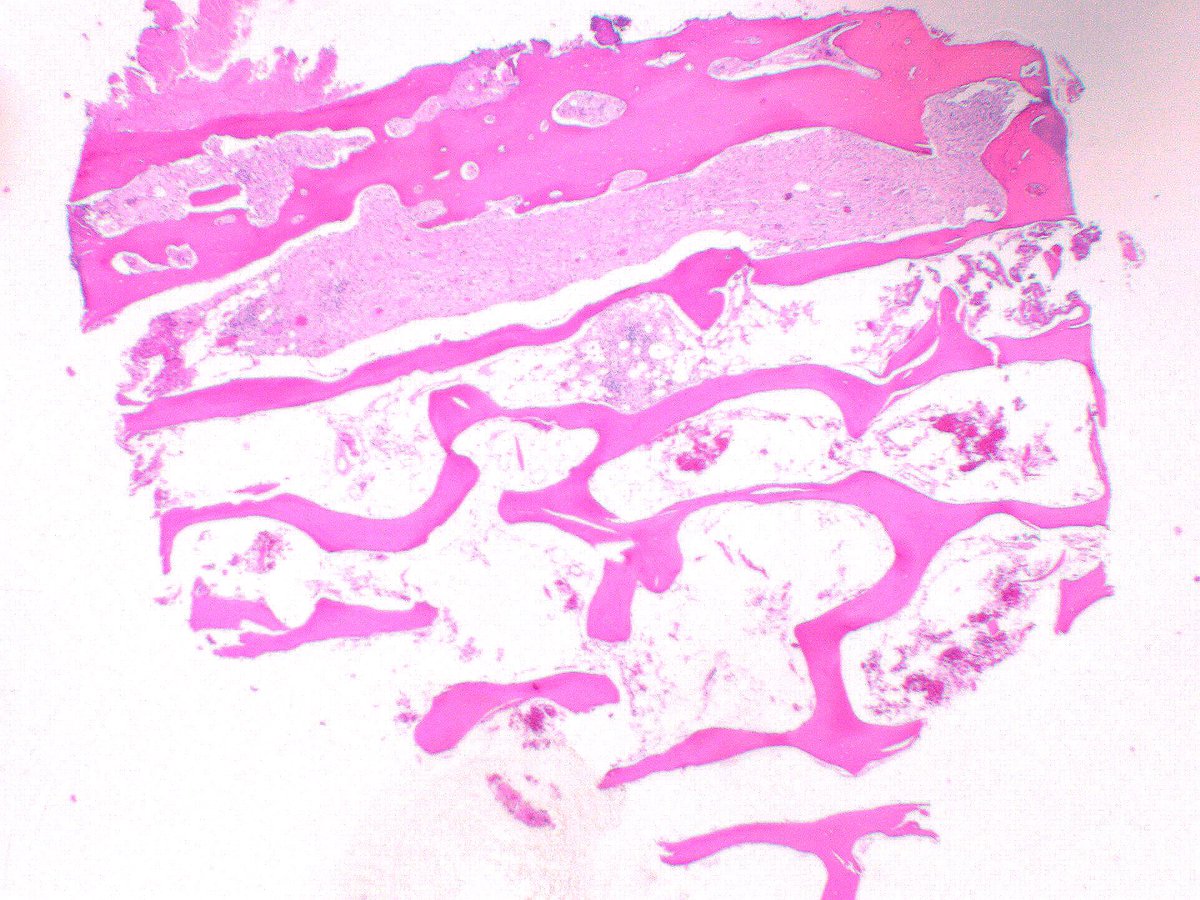

Cutaneous Kaposi sarcoma from 35yo M with HIV/AIDS #PathTwitter #pathology #dermpath #dermtwitter #patheducation #infectiousdisease Einstein Montefiore Pathology the New York Pathological Society Brian Cox, MD, MAS Anju Pandey Rebecca M. Marrero Rolon Rebecca Czaja Jerad Gardner, MD Tristan Rutland MBBS FRCPA IFCAP Olaleke Folaranmi